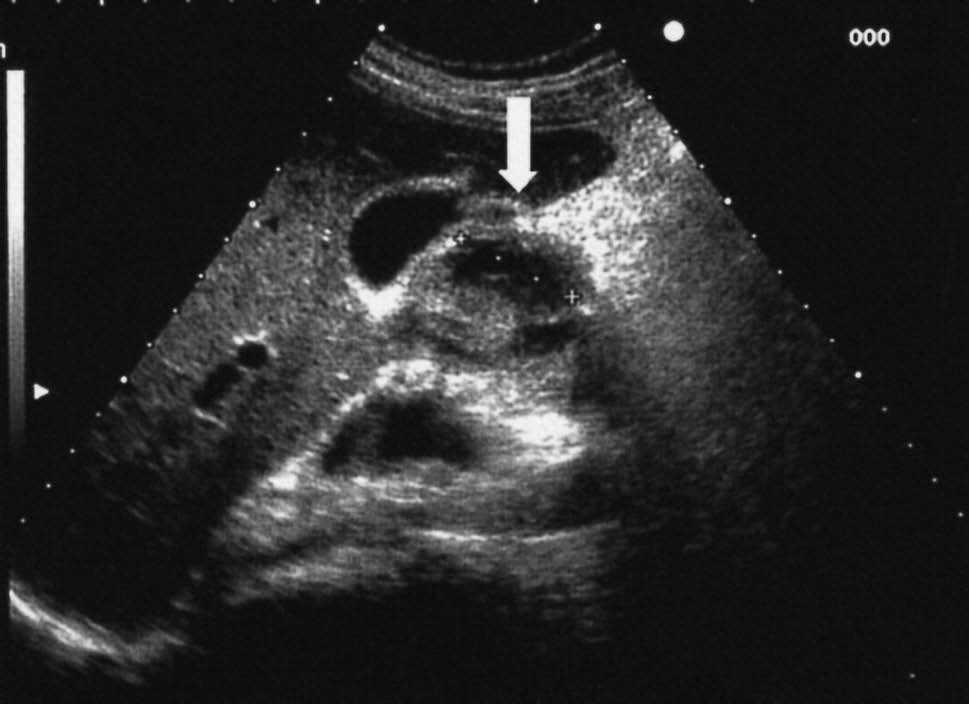

Inicialmente se decidió realizar una endoscopia digestiva alta que puso de manifiesto la existencia de una estenosis en la rodilla duodenal superior con pliegues engrosados, edematosos y congestivos que impedía la progresión del endoscopio. Las biopsias endoscópicas mostraron cambios inflamatorios inespecíficos. En estudios posteriores con ecografía abdominal y tomografía computarizada (TC) se pudo observar un engrosamiento de la pared duodenal y la existencia de lesiones quísticas en la propia pared engrosada (figs. 1 y 2). Para estudiar con detalle la estructura de la pared duodenal, y por la existencia de una estenosis que no permitía la progresión del endoscopio, se decidió realizar una exploración con minisondas ecográficas de 20 MHz, que puso de manifiesto cómo las lesiones quísticas dependían de la tercera capa (submucosa) del segmento duodenal engrosado (fig. 3).

Fig. 1. Ecografía abdominal. Engrosamiento de la pared duodenal con lesiones quísticas alargadas y bilobuladas rodeando la luz de manera semicircunferencial (flecha).